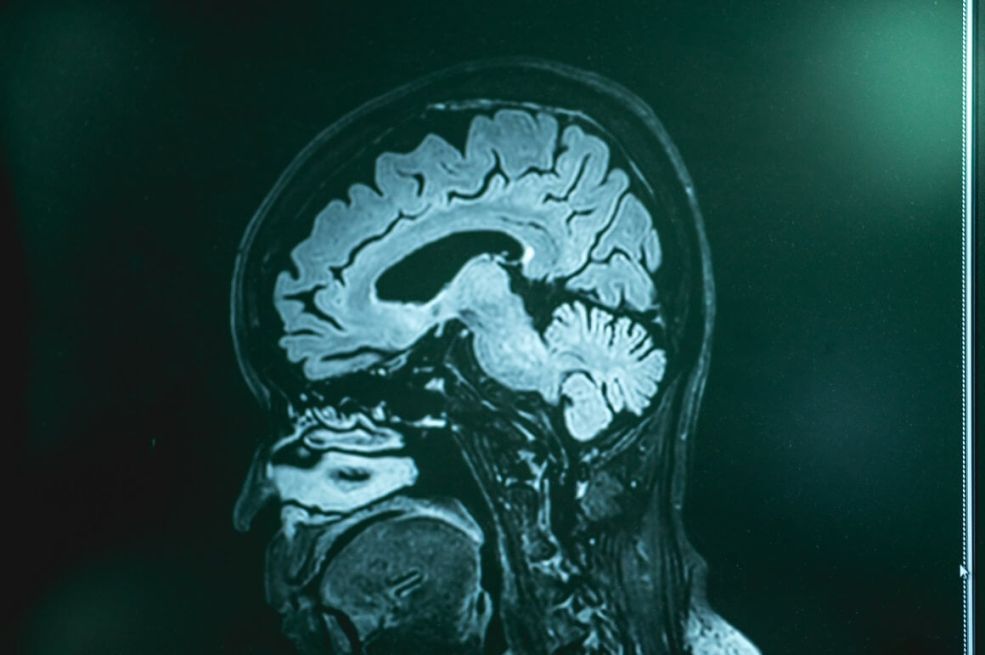

Demencija uzrokuje postupno opadanje kognitivnih funkcija, poput pamćenja, razmišljanja i sposobnosti obavljanja svakodnevnih aktivnosti.

Nedavne studije sugeriraju da određeni obrasci spavanja mogu povećati rizik od razvoja demencije. Na primjer, istraživanja su pokazala da osobe koje pate od apneje u snu, poremećaja karakteriziranog glasnim hrkanjem i učestalim buđenjem, mogu imati povećan rizik od demencije. Nedostatak kisika tokom spavanja može oštetiti moždane stanice i doprinijeti kognitivnom opadanju, prenosi Index.hr.